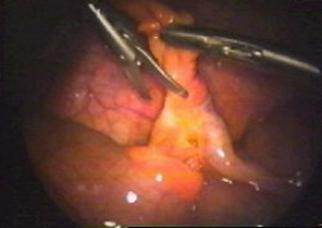

l in caz de apendicita acuta flegmonoasa, cu edem al mezoapendicelui, aplicarea unui clip este iluzorie deoarece artera nu este vizibila; in aceste cazuri se prefera scheletizarea mezoapendicelui in apropiere de insertia mezoului, prin electrocoagulare cu hook-ul sau foarfecele; daca, dupa disectia mezoapendicelui cu foarfecele sau cu hook-ul, bontul mezoapendicular sangera, se poate aplica pe el un nod Roeder;

l tratamentul este mai dificil in apendicita acuta perforata. Daca perforatia este distala, se poate diseca mezoapendicele cu ajutorul hook-ului sau cu foarfecele si se aplica un clip pe artera. Daca perforatia se gaseste la baza apendicelui, fie se

Fig. 20

va converti ( situatie in care incizia va fi plasata exact pe apendice ), fie se aplica doua fire pe portiunea distala a apendicelui juxtacecal, dincolo de perforatie sau, mai sigur, se poate aplica o pensa endo GIA de 30 mm. Acest stapler, introdus printr-un trocar de 12 mm din fosa iliaca dreapta, va aplica doua randuri de agrafe, pe mezoapendice si pe apendice. Daca perforatia este chiar la baza, aceasta pensa poate ridica putin din fundul cecal.

Fig. 21 Apendicectomie folosind Endo - GIA